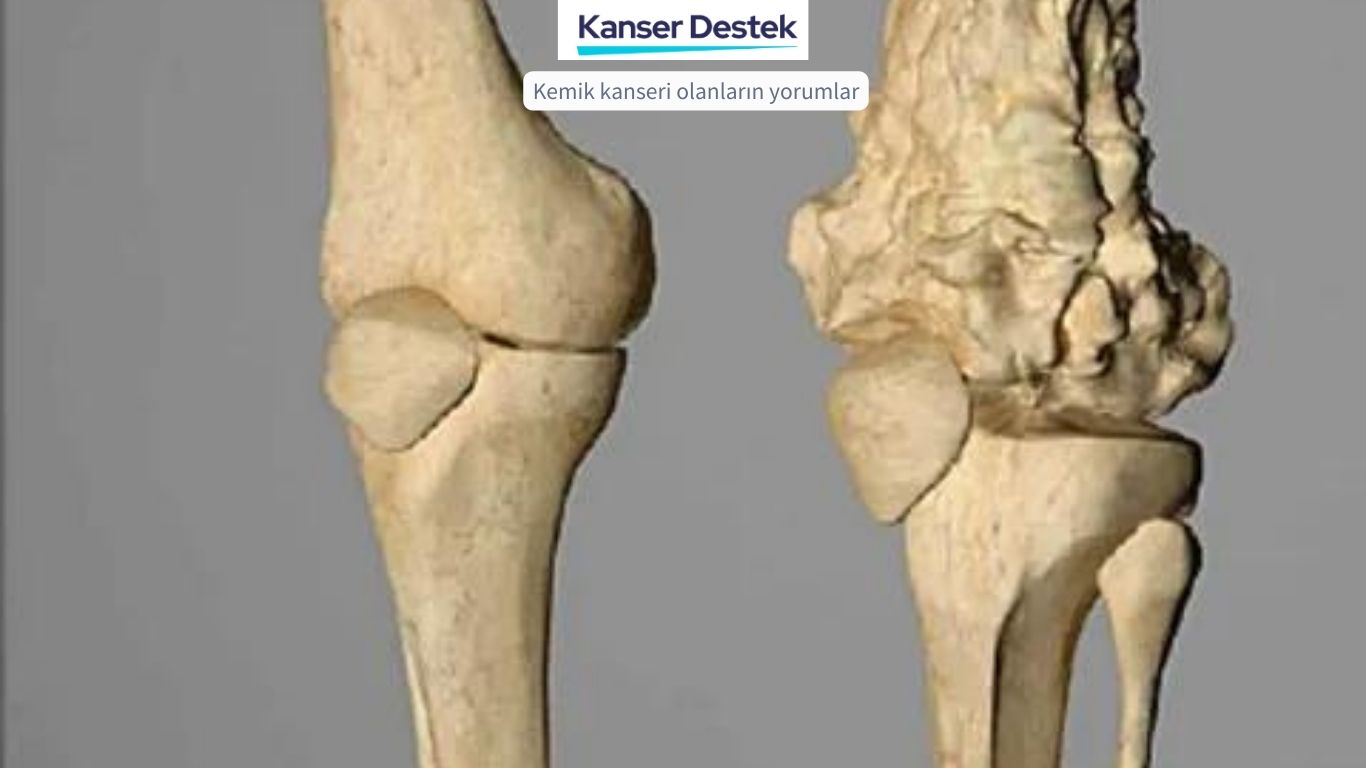

Diz kireçlenmesi, yani gonartroz ( latince genu: diz ve arthrosis: bozulma, harabiyet) eklem kıkırdağının aşınması ve harabiyeti sonucu eklem ağrısı ve hareket güçlüğü şeklinde ortaya çıkan karmaşık bir hastalıktır. Kireçlenme, halk arasında kullanılan çok da doğru olmayan bir ifade olup hastalığın son döneminde eklem kenarlarında oluşan kemik çıkıntılarını ve hareketsizliği tanımlar.

Diz kireçlenmesi, eklem kıkırdağına ek olarak menisküsler, eklem zarı, eklem sıvısının yapısı gibi ve hatta ilerleyen dönemlerde diz çevresi kaslarını da etkileyen, erken dönemlerden son döneme dek yıllar süren bir hastalıktır.

Kireçlenme ile sonuçlanan bir dizde, kemikler arasındaki boşluk azalırbu kemiklerin yüzeyini kaplayan parlak ve pürüzsüz kıkırdağın kaybı nedeniyle oluşur.

Röntgenler, ileri evre diz osteoartriti teşhisinde çok faydalıdır çünkü eklemin kendine özgü özellikleri vardır, bunlar arasında şunlar bulunur:

Kemikler arasındaki eklem boşluğunun azalması: Kıkırdak aşındıkça, aralarındaki eklem boşluğu genellikle daralır.

Kistler: Vücut kıkırdak yıkımına tepki verirken ve eklemi stabilize etmeye çalışırken, kemikte kistler veya sıvı dolu boşluklar oluşabilir. Artan kemik yoğunluğu ve eklem yüzeylerinde düzensizlik: Kemikler artık kıkırdak tarafından desteklenmediğinde, birbiri içine geçecek sürtünme yaratacaktır. Vücut, buna karşılık daha fazla kemik dokusu üreterek yanıt verecek, bu da kemik yoğunluğunu arttıracaktır. Bu kemiklerde nerdeyse mermer sertliğinde esnek olmayan bir yapıya neden olur. Artan kemik dokusu, aynı zamanda eklem yüzeylerinde düzensizliklere ve eklemde ağrılı kemik çıkıntılarına oluşmasına yol açar.